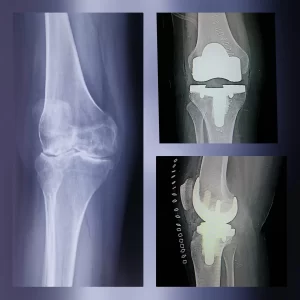

- Osteotomia: Consiste en la realización de un corte controlado en la tibia o el fémur para corregir o cambiar el eje de carga y de esa manera, aliviar el dolor, función y los síntomas como consecuencia del desgaste en una parte de la articulación.

Se realiza en rodillas con una artrosis o desgaste de un compartimento y en gente joven y activa.

- Prótesis total o parcial de rodilla: Consiste en la sustitución parcial o total de las superficies articulares desgastadas para restablecer la función de la rodilla.